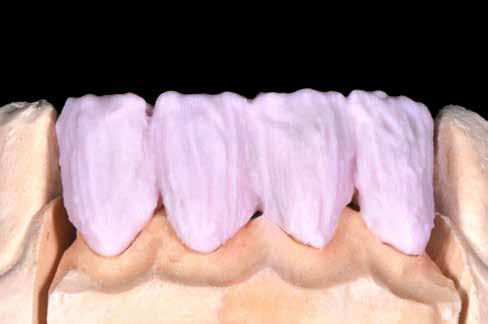

ás, majd #0-ás retrakciós fonalakat (Ultrapak, Ultradent Products Inc, South Jordan, Utah, Egyesült Államok) helyeztünk. A végső precíziós lenyomatot polivinil-sziloxán lenyomatanyaggal (Virtual 380, Ivoclar Vivadent AG, Schaan, Liechtenstein) vettük. A fogtechnikai fázisban ultravékony (0,5 mm-nél vékonyabb) földpátkerámia héjak elkészítését kértük (Super Porcelain Ex-3, Kuraray Noritake Dental, Tokió, Japán), (7. ábra). A kerámia héjak készre vitelét követően a próba során a héjakat a helyükre illesztettük a széli zárást, az így kialakított fogformák ellenőrzése céljából. A páciens elégedett volt az így kapott látvánnyal. A végleges ragasztás kofferdám izolálásban történt. A preparált fogak felületét először 37%-os foszforsavval (Total Etch, Ivoclar Vivadent) 15 másodpercen keresztül kondicionáltuk, majd vízzel leöblítettük (8. ábra). A kondicionált zománcfelszíneket Adhese Universal (Ivoclar Vivadent) adhezívvel kezeltük. A kerámiahéjak homorú felszíneit 5%-os folysavval (IPS Ceramic Etching Gel, Ivoclar Vivadent) 20 másodpercen át kondicionáltuk, majd a felszíneket Monobond Plus primerrel (Ivoclar Vivadent) vontuk be (7. és 8. ábrák). A héjakat fényre kötő rezinalapú ragasztócement (Variolink Esthetic LC, Ivoclar Vivadent) applikálását követően a helyükre illesztettük. A kifolyó cementfelesleg eltávolítását követően minden felszínt (labiális, palatinális, meziális és distális) LED-es polimerizációs lámpával (VALO Cordless, Ultradent) 40 másodpercen keresztül megvilágítottuk.

Az elmúlt években a fogtechnikai eljárások fejlődésének köszönhetően lehetőségünk van nagy szilárdságú kerámiákból készülő ultravékony kerámia héjak készítésére.20 Jelen esetben, a kimagasló esztétikai tulajdonságainak köszönhetően, a földpátkerámiára esett a választásunk. Azt is fontos azonban kiemelni, hogy jelenleg csak kisszámú esetismertetésben találkozhattunk földpátkerámiából készült ultravékony héjakkal. Egy anyagtani vizsgálatban arról számoltak be, hogy az ultravékony (0,5 mm-nél vékonyabb) kerámiahéjak töréssel szembeni ellenálló képessége lehetővé teszi a klinikai felhasználásukat.21 Az utóbbi időben a rezin alapú ragasztócementek kötő- és mechanikai ereje javult18,22, ezáltal az ezekkel az anyagokkal rögzítésre kerülő restaurátumok

mechanikai tulajdonságai jobbak lettek. Ez is hozzájárult ahhoz, hogy lehetőségünk van az 0,5 mm-nél vékonyabb ultravékony héjak földpátkerámiából történő elkészítésére. A négyéves utánkövetés azt igazolta, hogy ultravékony héjakkal megfelelő eredményeket lehetett elérni.